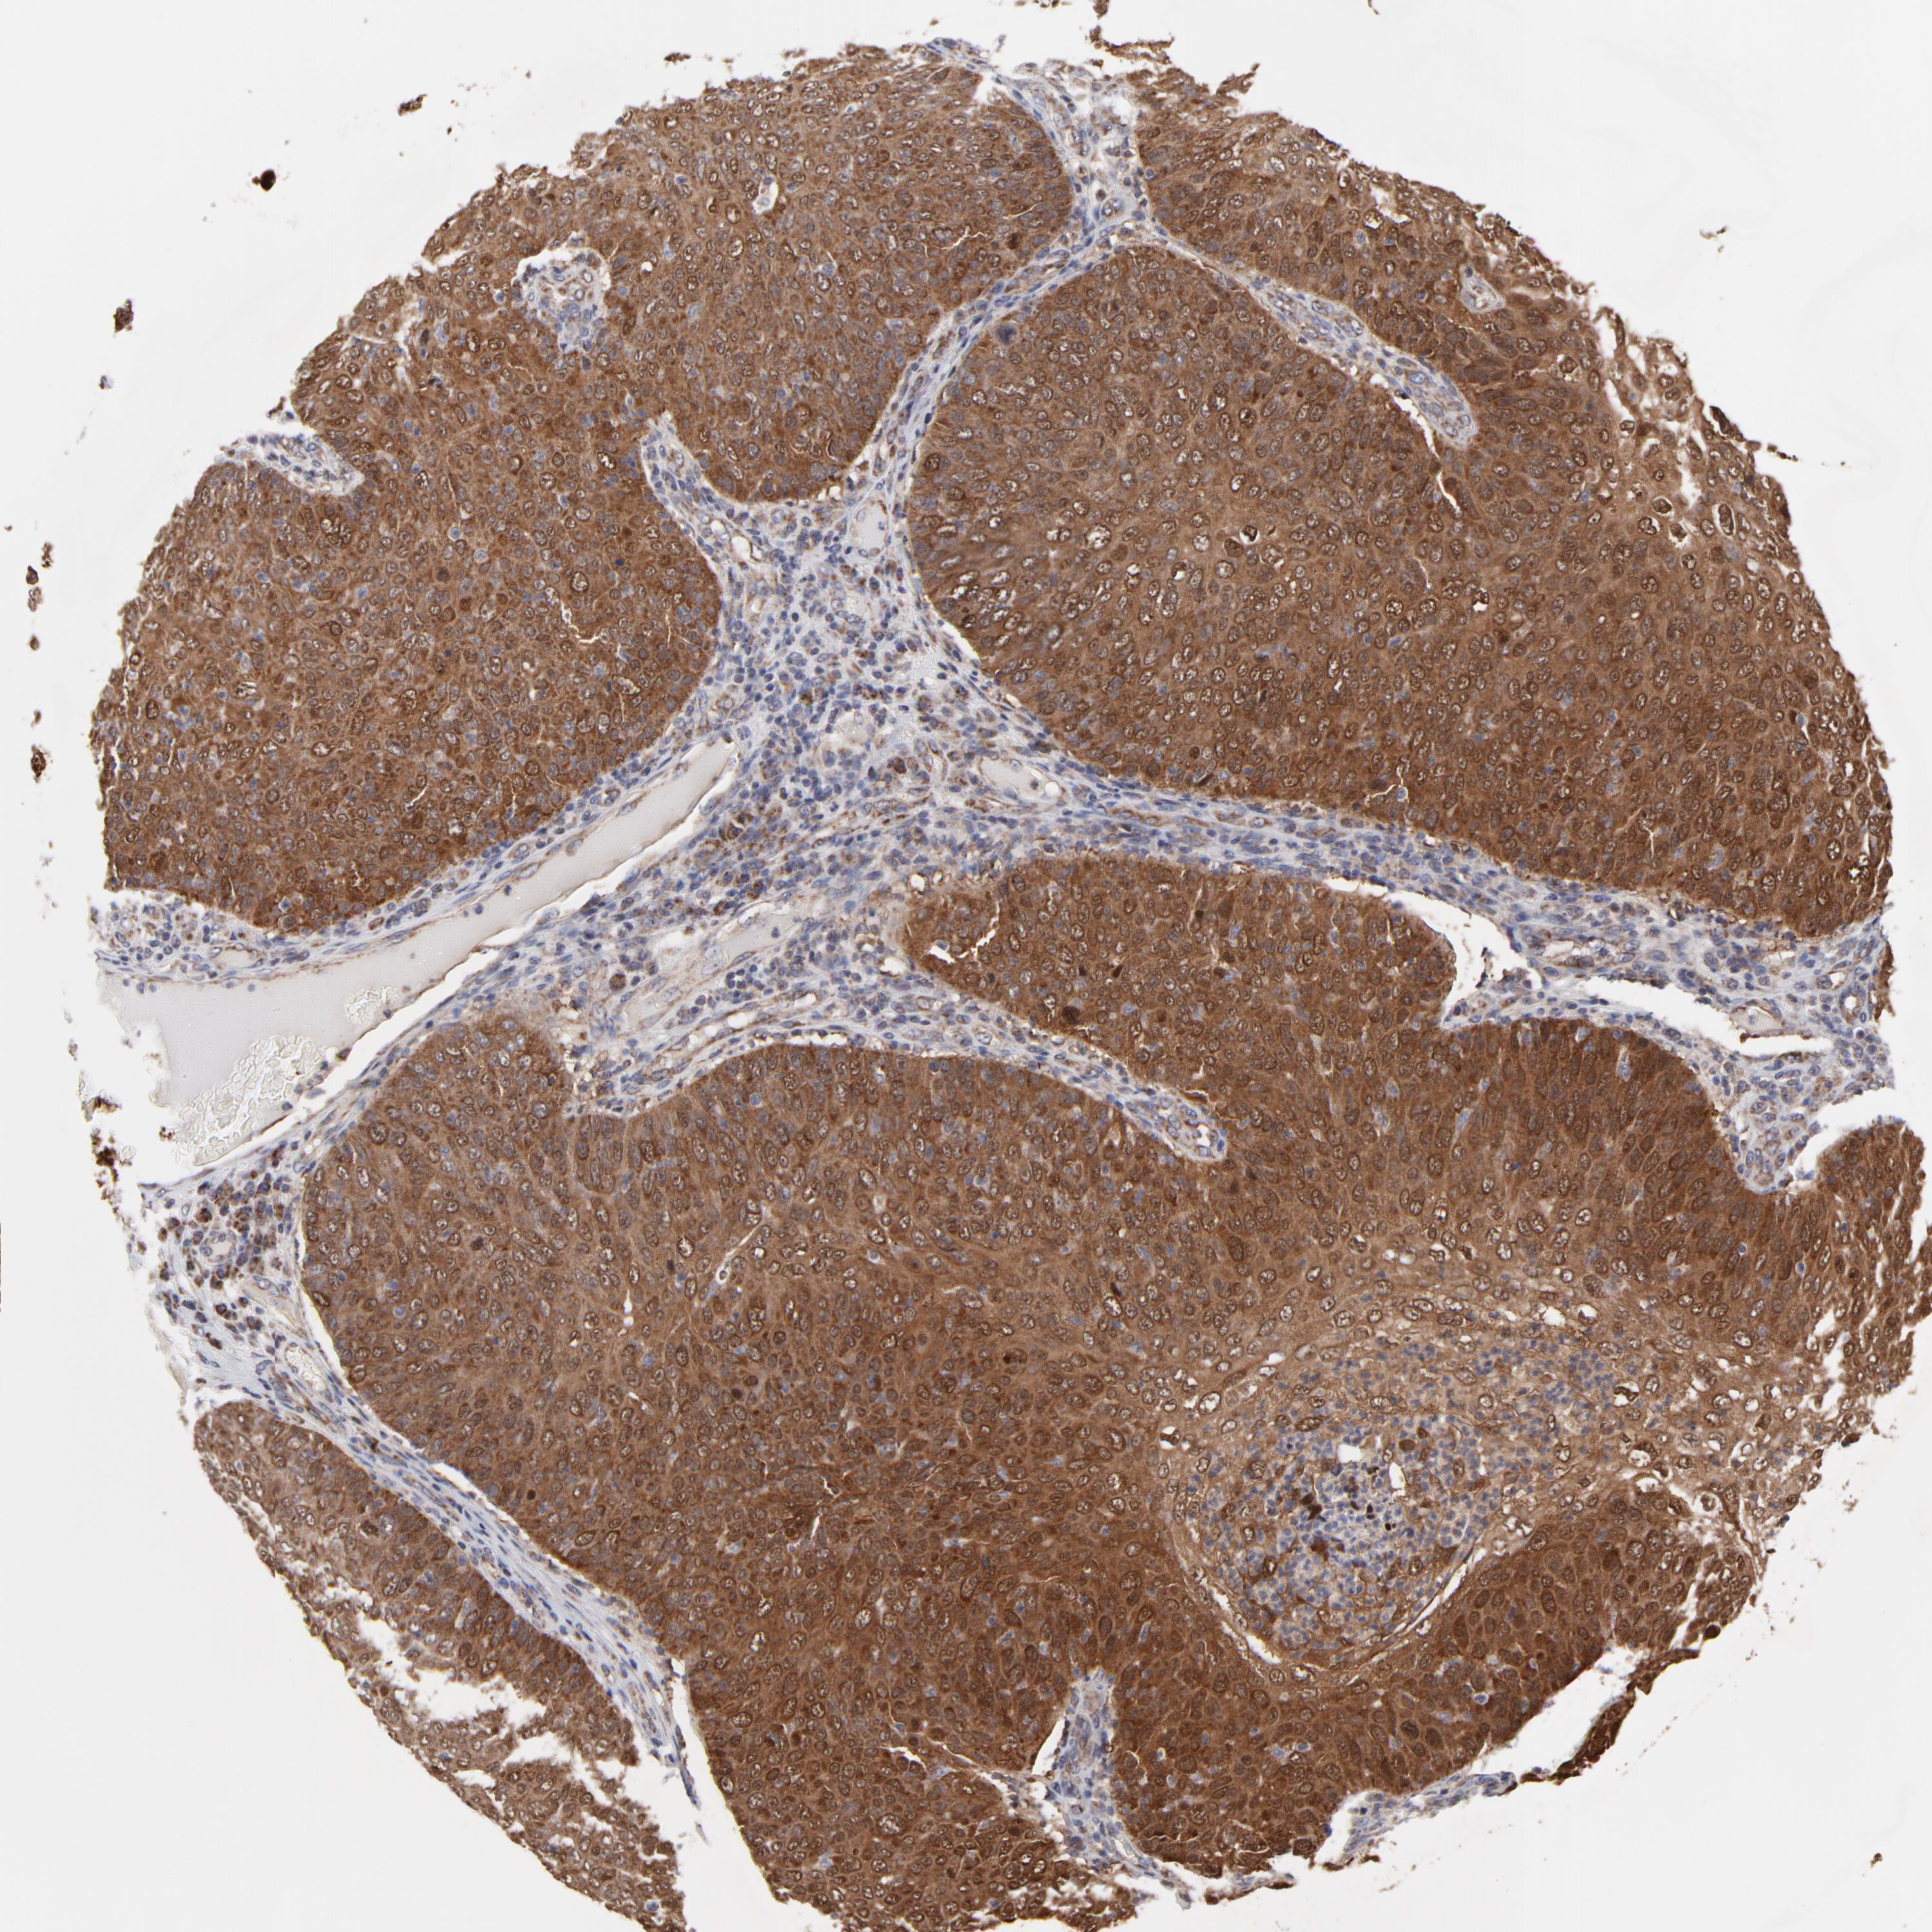

SKIN CANCER - Protein expressioni

A mouse-over function shows sample information and annotation data. Click on an image to view it in a full screen mode. Samples can be filtered based on level of antibody staining by selecting one or several of the following categories: high, medium, low and not detected. The assay and annotation is described here.

Antibody stainingi

Antibody staining in the annotated cell types in the current human tissue is reported as not detected, low, medium, or high, based on conventional immunohistochemistry profiling in selected tissues. This score is based on the combination of the staining intensity and fraction of stained cells.

Each image is clickable and will lead to virtual microscopy that enables deeper exploration of all samples and also displays staining intensity scores, fraction scores and subcellular localization as well as patient and tissue information for each sample.

Antibody HPA003251

Staining

High

Medium

Low

Not detected

Intensity

Strong

Moderate

Weak

Negative

Quantity

>75%

75%-25%

<25%

None

Location

Nuclear

Cytoplasmic/membranous

Cytoplasmic/membranous,nuclear

Squamous cell carcinoma, NOS

Basal cell carcinoma